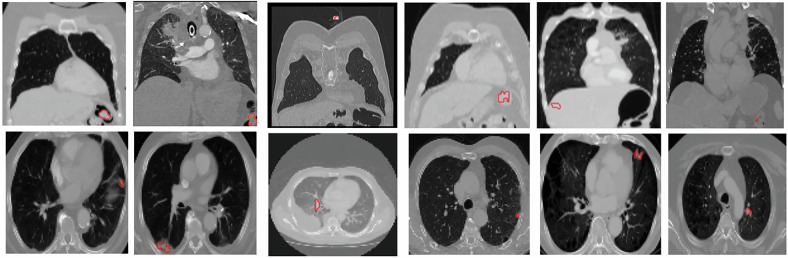

Materials and methods: We analyzed 1,081 retrospectively collected CT scans with 5,322 annotated lesions (4.92 ± 13.05 lesions per scan). The cohort was stratified into training (n = 868) and testing (n = 213) subsets. We developed an automated three-step pipeline, including thoracic bounding box extraction, multi-instance lesion segmentation, and false positive reduction via a novel multiscale cascade classifier to filter spurious and non-lesion candidates.

背景:计算机断层扫描(CT)对肺癌病变的准确分割对于精确诊断、个性化治疗计划和治疗反应评估至关重要。虽然对原发性肺病变的自动分割已经得到了广泛的研究,但对每个患者的多个病变进行分割的能力仍未得到充分的探索。在这项研究中,我们通过引入一种新颖的自动化方法来解决这一差距,该方法用于肺癌病变的多实例分割,利用具有真实世界多中心数据的异质队列。材料和方法:我们回顾性分析了1,081份CT扫描,其中包含5,322个注释病灶(每次扫描4.92±13.05个病灶)。该队列被分为训练组(n = 868)和测试组(n = 213)。我们开发了一个自动化的三步流水线,包括胸围框提取,多实例病变分割,以及通过一种新的多尺度级联分类器过滤虚假和非病变候选物来减少假阳性。结果:在独立测试集上,我们的方法实现了分割的Dice相似系数为76%,病灶检测灵敏度为85%。当在188个真实案例的外部数据集上进行评估时,它的Dice相似系数为73%,病变检测灵敏度为85%。结论:我们的方法在CT扫描上准确地检测和分割了每位患者的多个肺癌病变,在独立测试集和外部真实数据集上显示了稳健性。相关声明:人工智能驱动的病灶分割全面捕捉病灶负担,增强肺癌评估和疾病监测。重点:多实例肺癌病灶自动分割尚未被充分探索,但对疾病评估至关重要。开发了一种基于深度学习的分割管道,训练了多中心真实世界的数据,在外部验证中灵敏度达到85%。胸廓边界盒和假阳性减少技术提高了管道的分割性能。